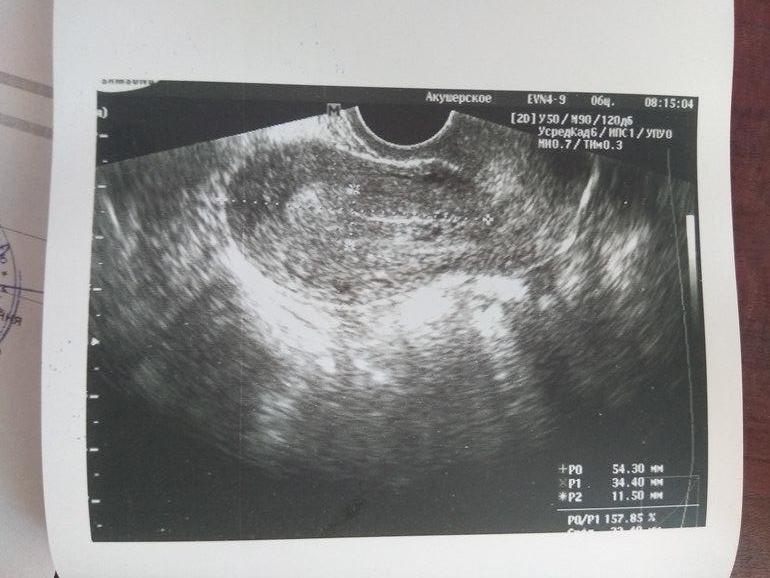

Вчера выкладывала тесты,сегодя узи. Матка без патологий,эндометрий 11,5. шейка матки открыта,как при овуле, желтого тело гинеколог не увидела.сказала,что и беременности не видит(( (( хгч утром сдала,вечером будет результат